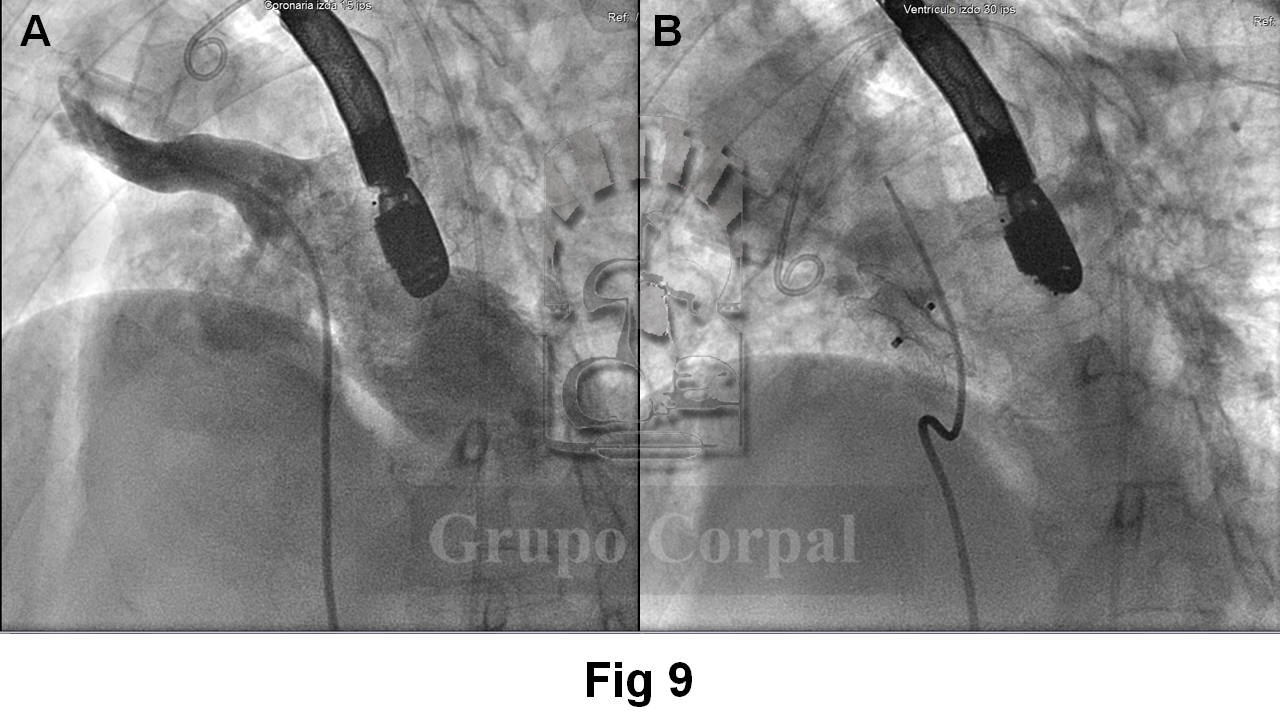

La Figura 8 muestra 2 instantes de esa angiografía en la que se opacifican tenuemente las cavidades izquierdas, sin observarse contaminación del lado derecho. La Figura 9 muestra el resultado angiográfico, con imagen antes del tratamiento (A) y después de la suelta (B).